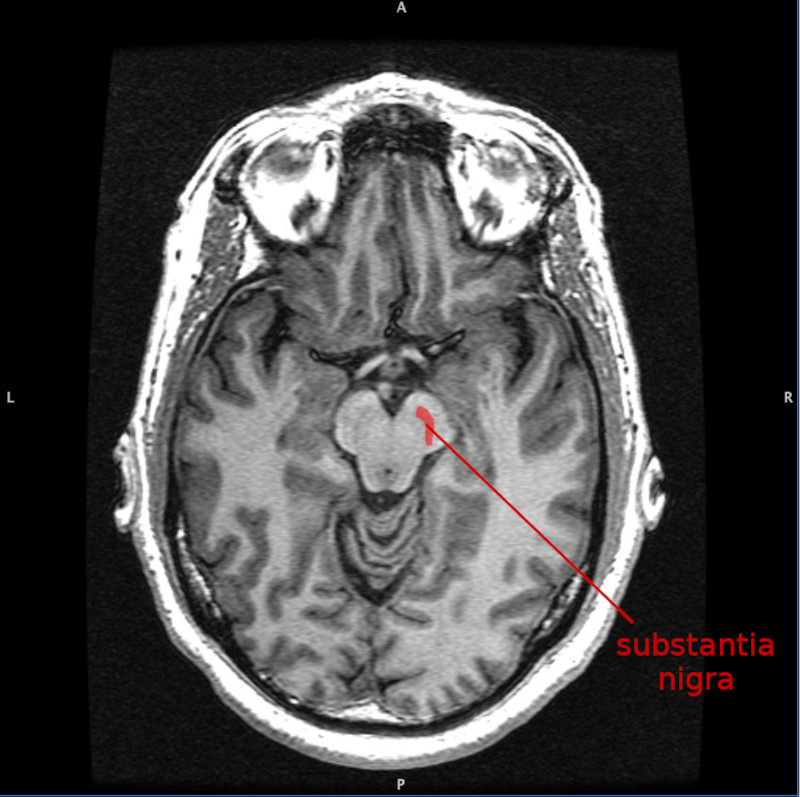

La morte delle cellule della substantia nigra, una regione mesencefalica, sembra essere all'origine del disturbo poiché esse compartecipano alla produzione della dopamina. Le ragioni per le quali le cellule muoiono sono di fatto sconosciute ed entrano in gioco i fattori di rischio, anche i più banali e onnipresenti come sostanze tossiche, traumi cranici e fattori genetici. Si è poi scoperto che chi fuma e beve caffè ha un minor rischio di contrarre la malattia!

La substantia nigra, insieme ad altri quattro nuclei, fa parte dei gangli basali, che si trovano nel mesencefalo, posteriormente ai peduncoli cerebrali. Sono strutture pari, una a destra ed una a sinistra.